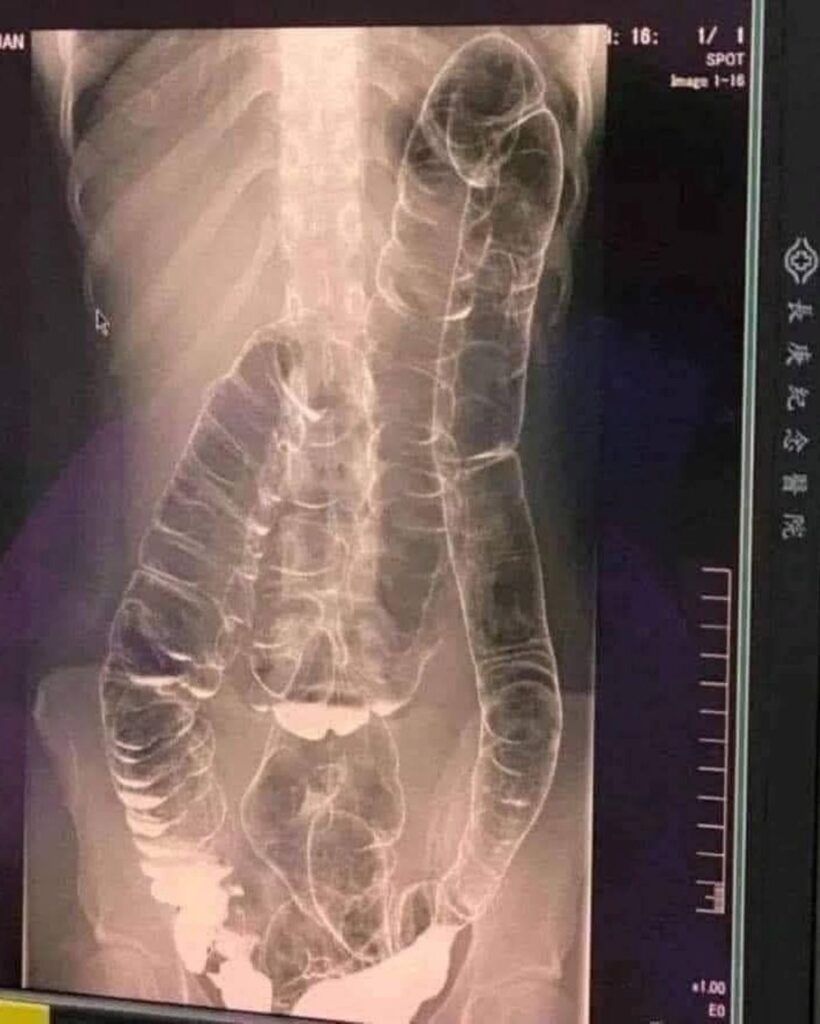

O tânără care a ignorat ani la rând semnele constipației a fost transportată de urgență la spital după ce nu avusese niciun scaun timp de peste două săptămâni. Investigațiile imagistice au arătat un tablou medical îngrijorător: colonul ajunsese atât de dilatat încât urca până aproape de inimă. Radiografia a surprins un organ complet deformat, lipsit de pliurile caracteristice, un semn clar al unei presiuni interne extreme.

Atunci când reziduurile rămân prea mult timp în intestin, colonul este forțat să se dilate pentru a face loc. În acest caz, acumularea excesivă a dus la întinderea severă a pereților intestinali. Colonul, în mod normal un tub flexibil și ondulat, ajunsese complet neted și rigidizat.